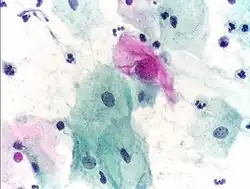

Normal endocervical cells should be present into the slide, as a proof of a good quality sampling

An obviously atypical cell can be seen